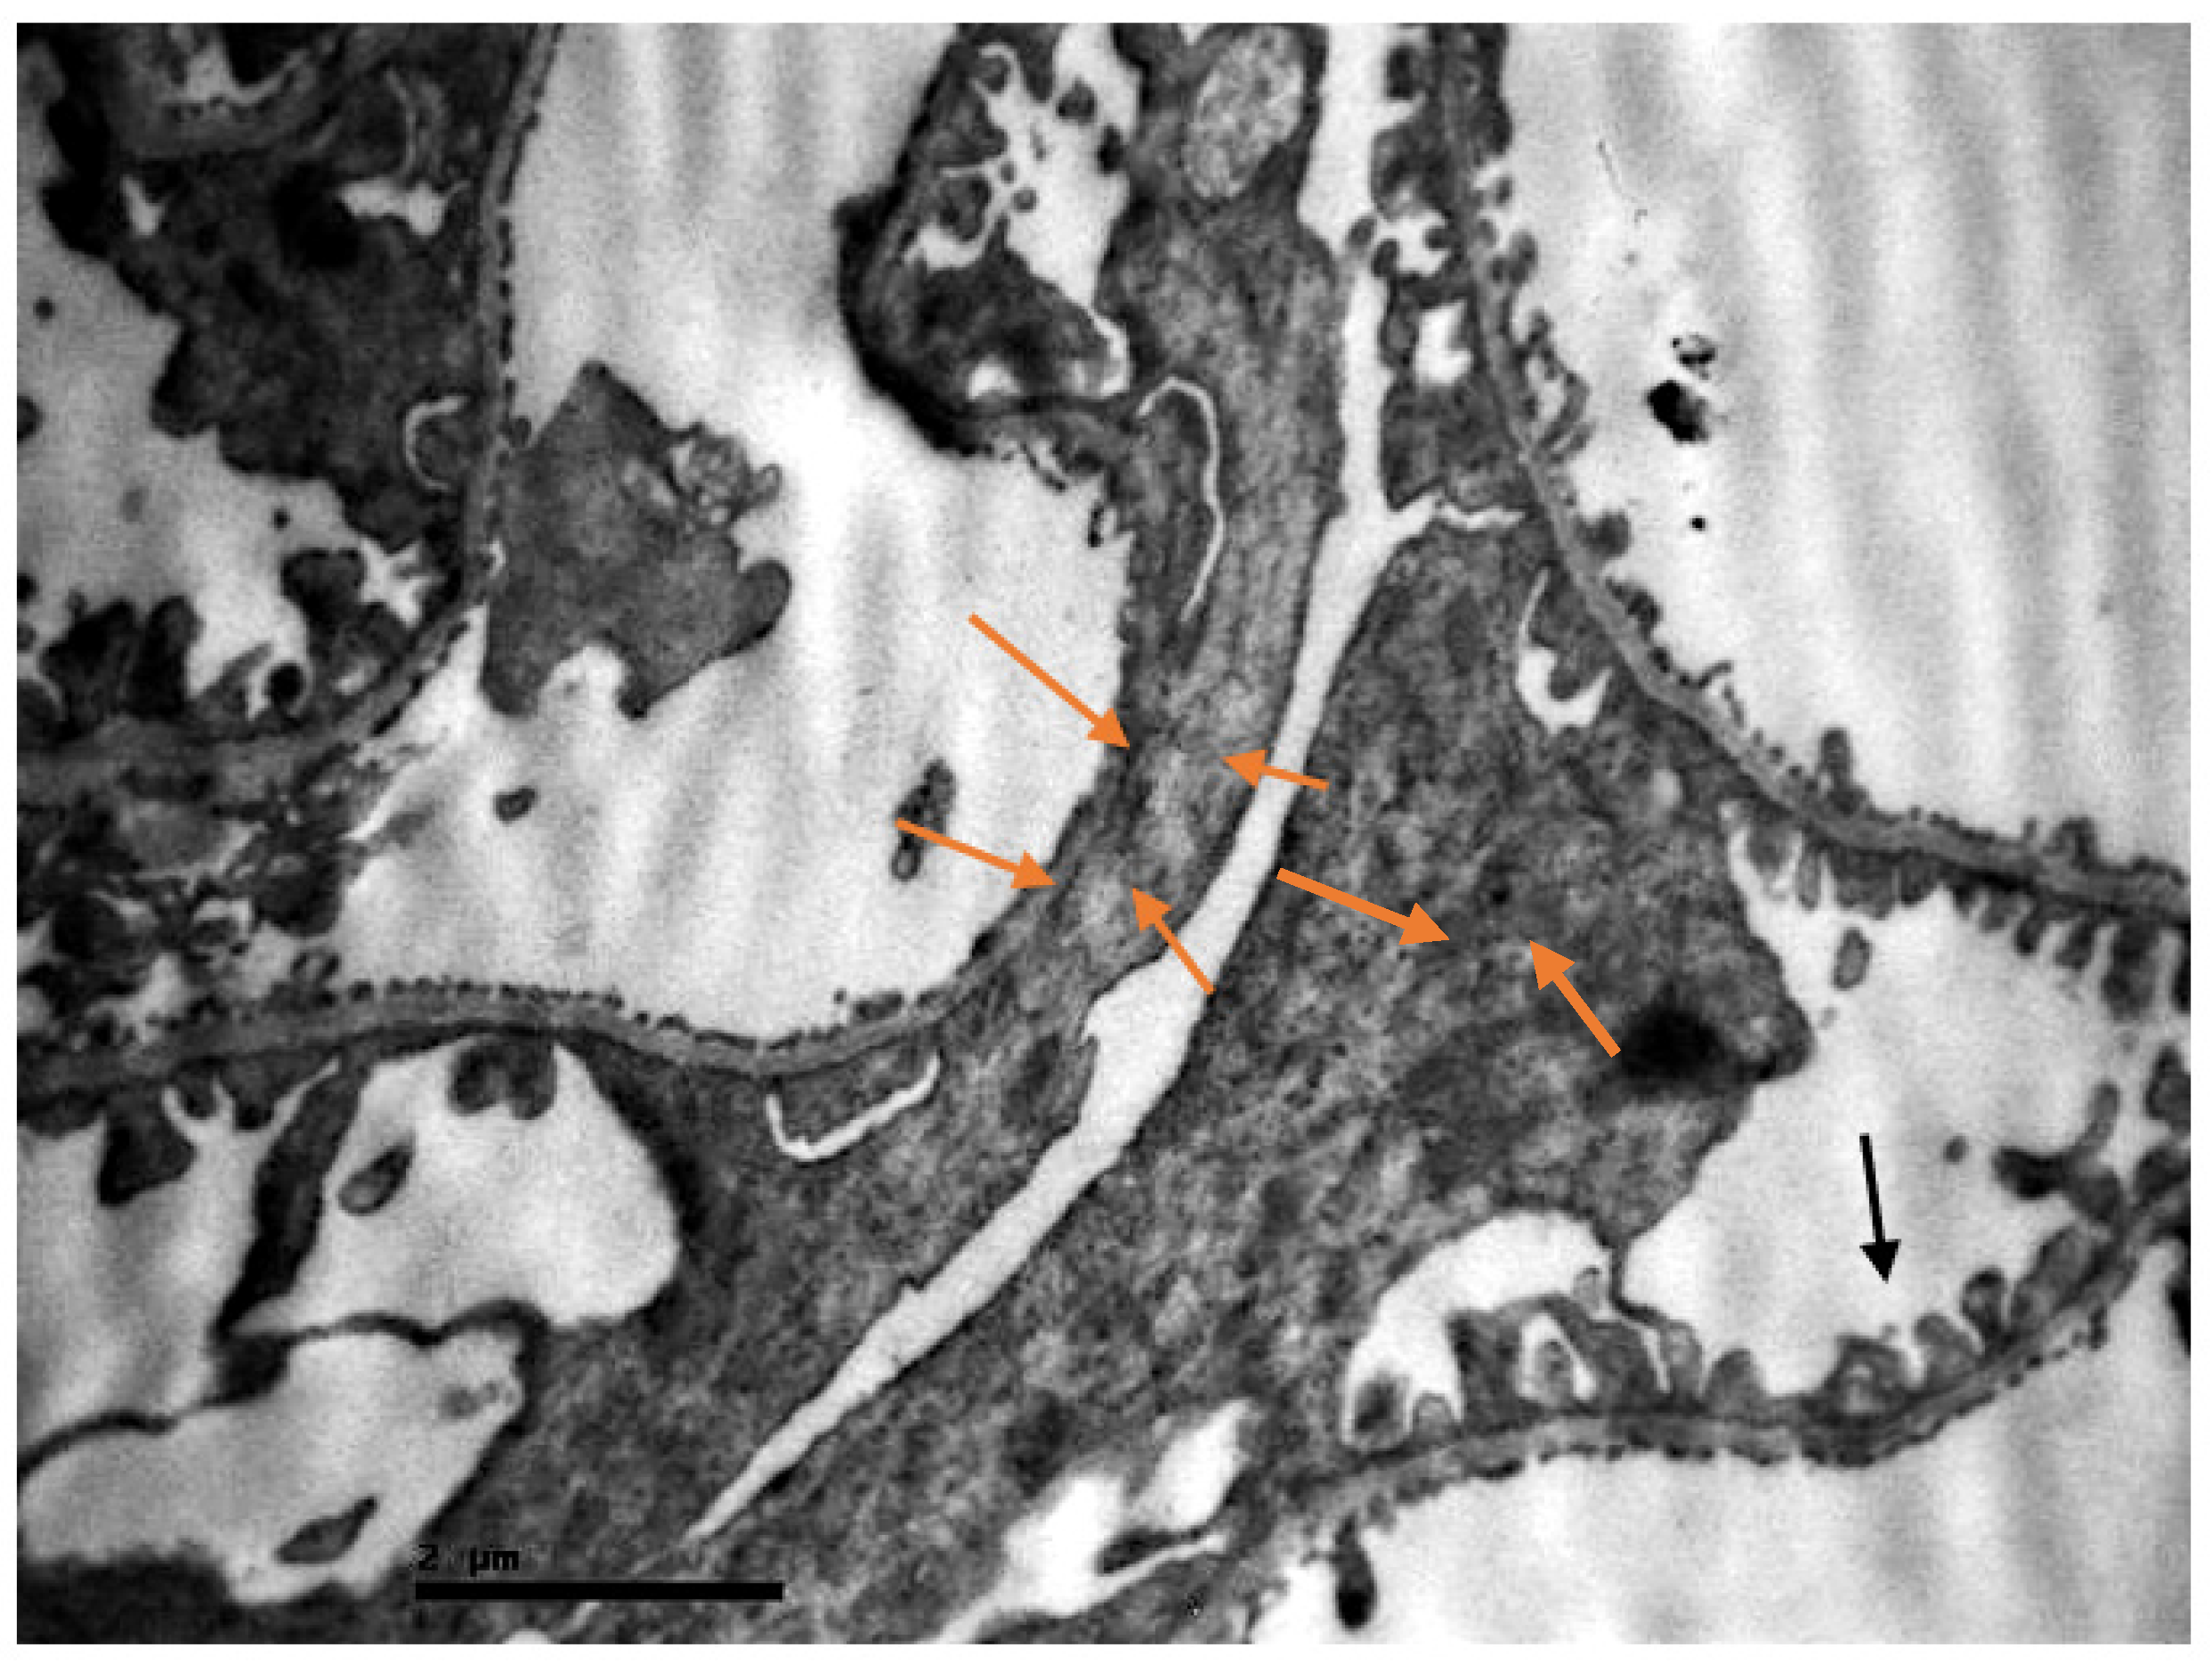

2.2. Electron Microscopic Evaluation